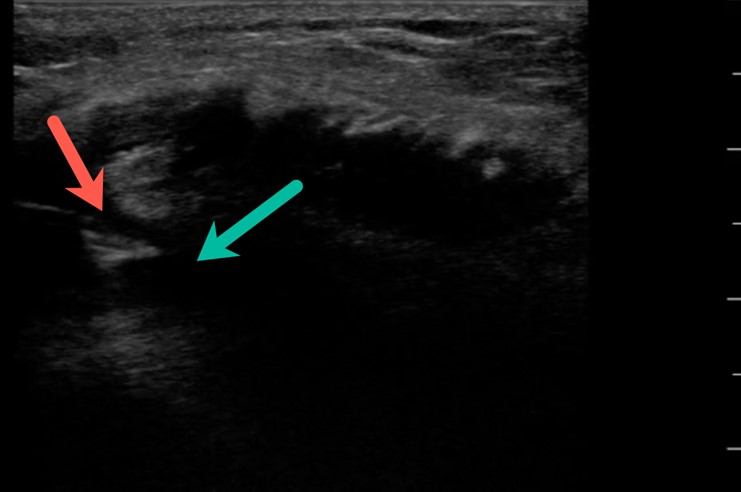

Using the high-frequency linear probe, typical views are obtained superior and inferior to the patella, as well as medial, lateral, and posterior to the knee joint. Views superior and inferior to patella assess for the integrity of the quadriceps and patellar tendons, the patella, as well as presence of knee effusion. Normal examination of the overlying skin and absence of cobblestoning of the soft tissue on ultrasound lessens the likelihood of cellulitis and abscess. Figure 1 shows the anterior ultrasound view of the knee, the patella. An intact patella should demonstrate the uninterrupted hyperechoic curvature of the cortical surface. In figure 1, we see an unmistakable cortical disruption (between the two red arrows), indicating a patellar fracture. Knee effusions will appear as an anechoic collection, indicated by the blue arrow, deep to the tendons. (Fig. 2) Medial and lateral views can also demonstrate effusions. Complex effusions such as hemarthrosis appear as hypoechoic collections if clotting has occurred. Figure 3 demonstrates a traumatic hemarthrosis identified by the green arrow. Figure 4 shows another simple knee effusion, indicated by the green arrow, without a history of trauma. Aspiration in the emergency department or office can be useful in directing therapy. In Figure 4, we see the needle approaching the effusion from the left side of the screen highlighted by the red arrow. Lastly, the posterior aspect of the knee contains the popliteal vessels. The popliteal vessels should be identified by Color Doppler, allowing differentiation from the non-vascular structures. Figure 5 shows a cystic non-compressible, anechoic structure without internal echoes within the popliteal fossa highlighted by the yellow arrow.

Figure 4